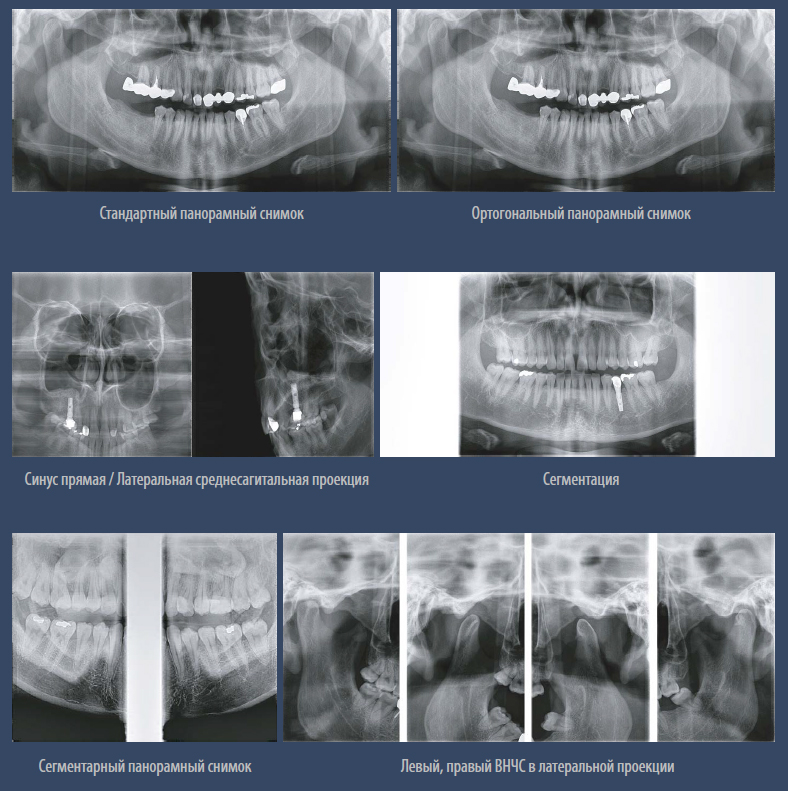

Панорама

Высокое разрешение при панорамной съёмке.

Мульти фокус.

Функция используется в режиме панорамы. Технология мульти фокуса позволяет добиться максимального качества, максимальной глубины резкости и захвата всей зоны сканирования при помощи пяти фокусных слоев.

Режимы экспозиции панорамной съёмки.

– Стандартный панорамный

– Ортогональный панорамный

– Сегментарный панорамный

– Горизонтальные и вертикальные сегменты

– Прямая проекция ВНЧС

– Детский панорамный

– Левый, правый ВНЧС в латеральной проекции

– Левый, правый ВНЧС прямая и латеральная проекции

– Синусы латеральная и прямая проекции